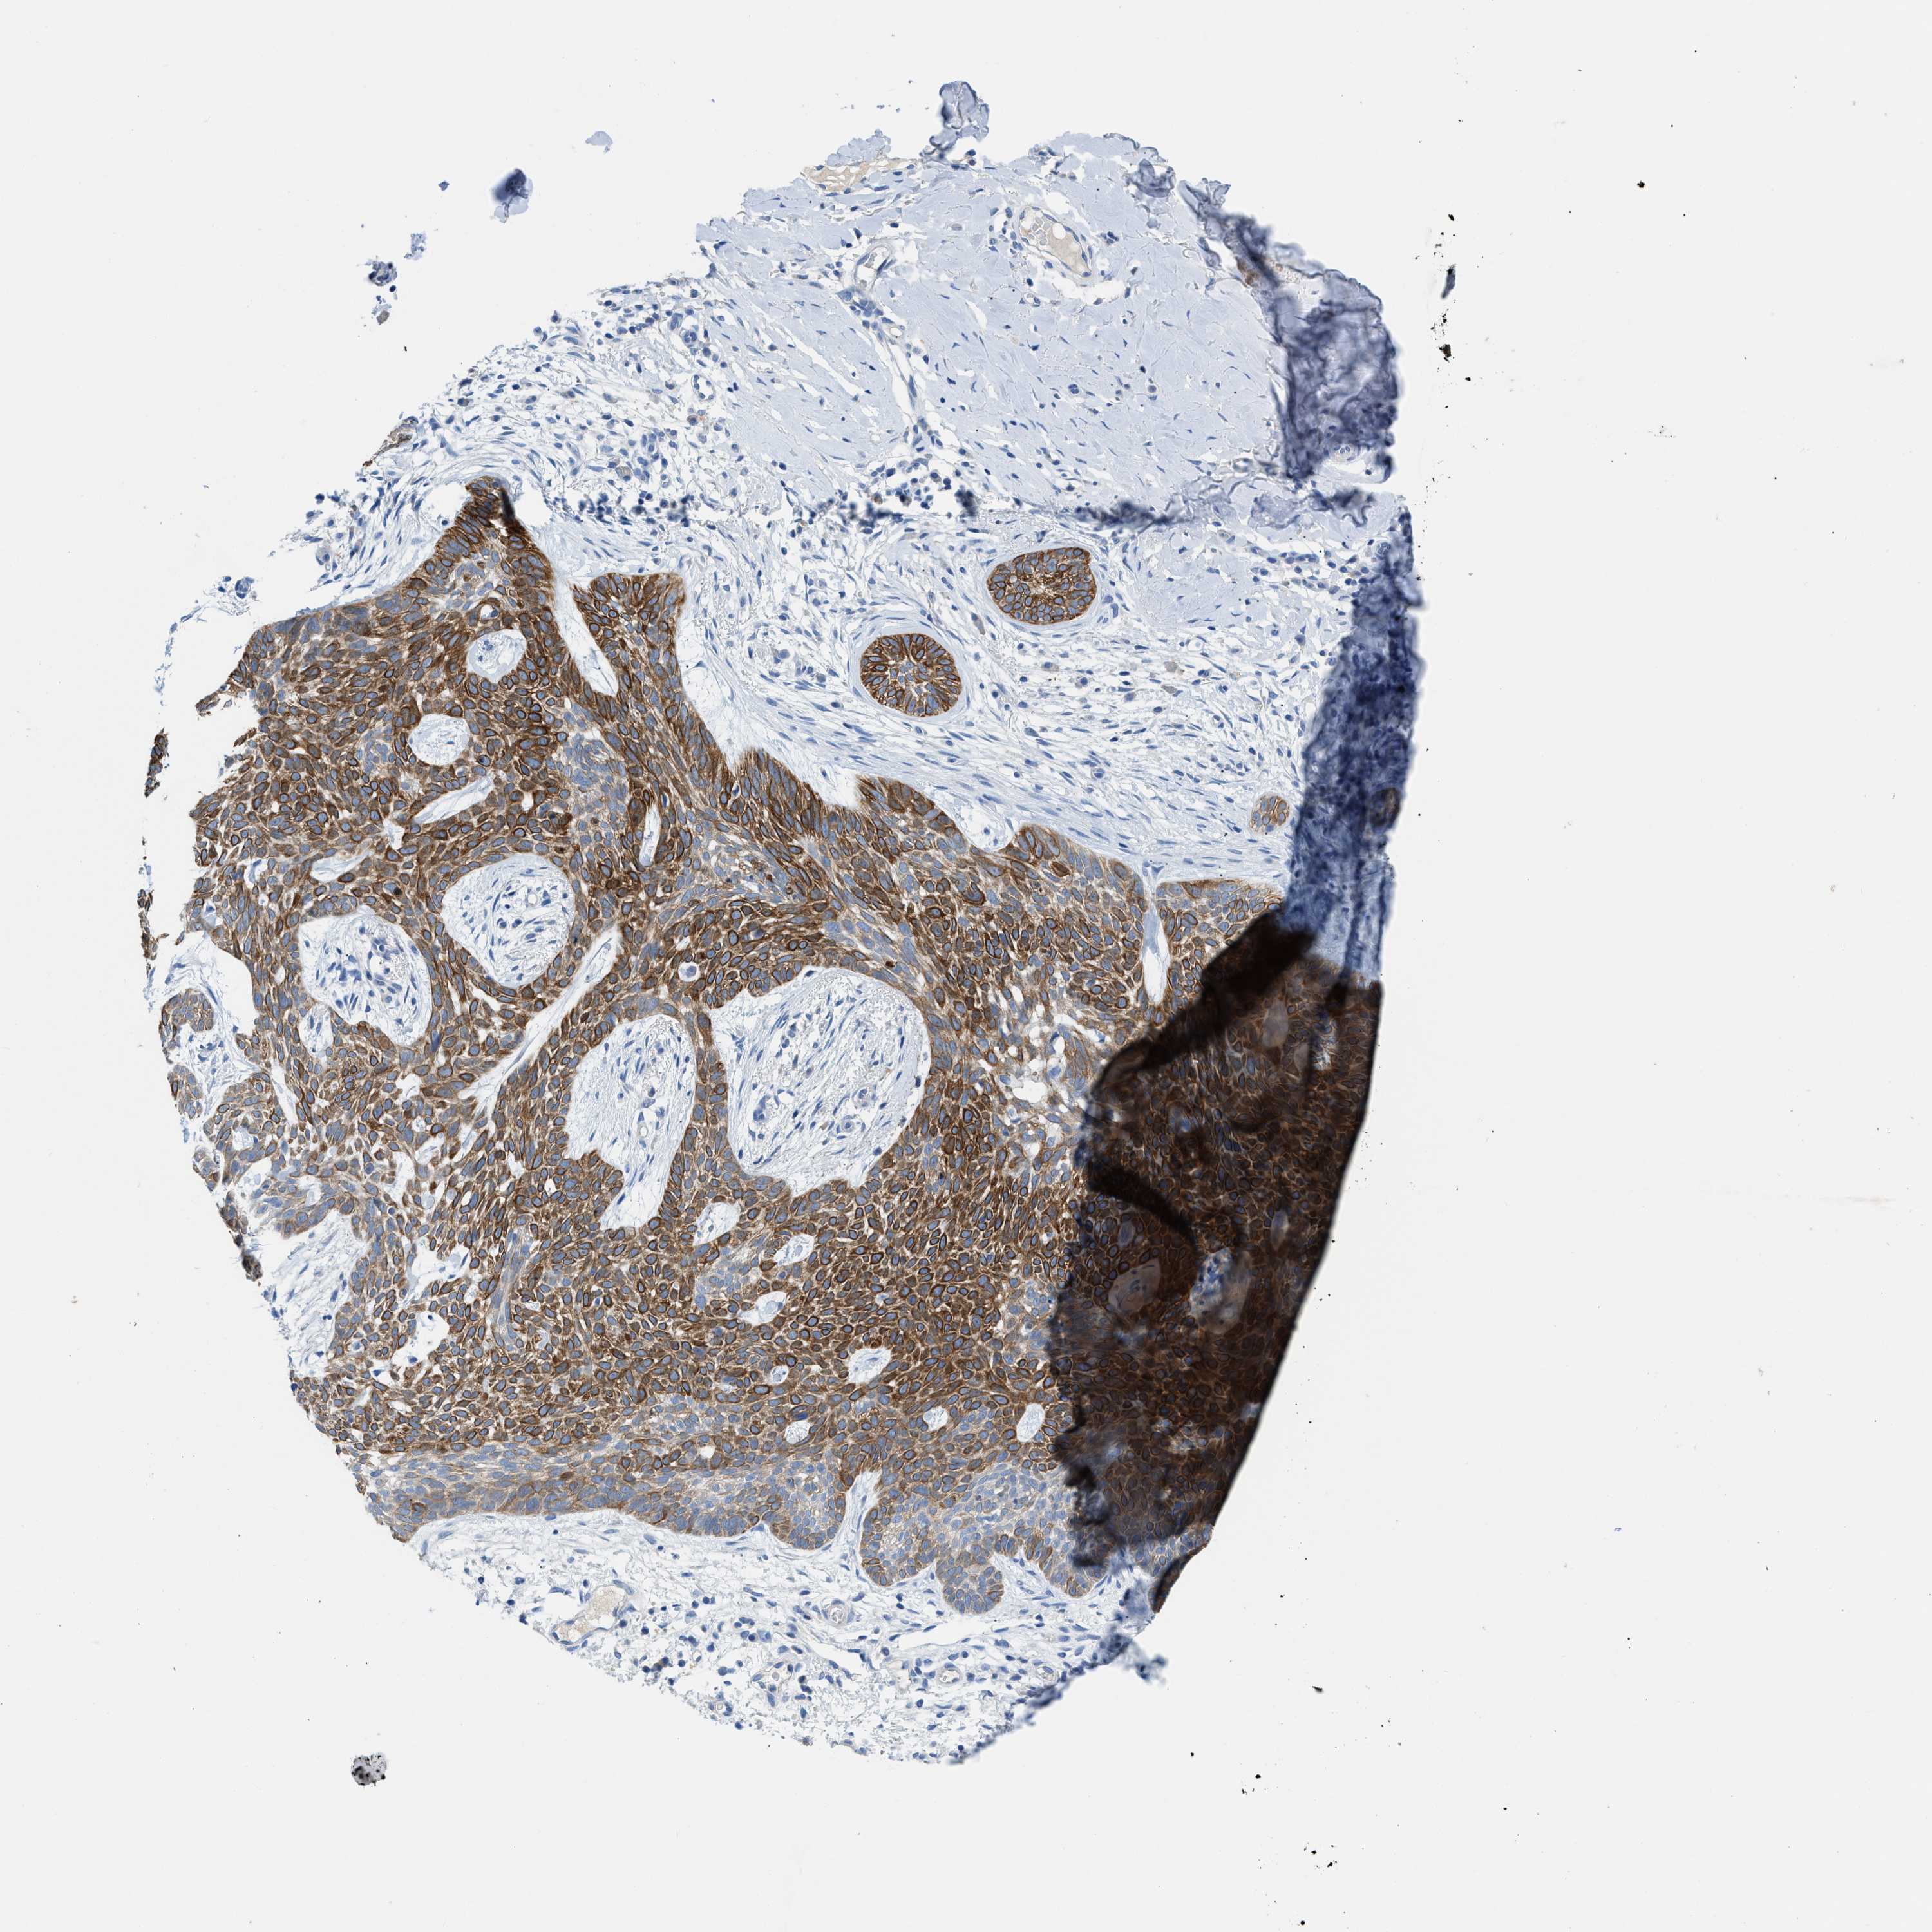

CANCER SKIN CANCER Show tissue menu

Basal cell and squamous cell cancer

SKIN CANCER - Protein expressioni

A mouse-over function shows sample information and annotation data. Click on an image to view it in a full screen mode. Samples can be filtered based on level of antibody staining by selecting one or several of the following categories: high, medium, low and not detected. The assay and annotation is described here.

Each image is clickable and will lead to virtual microscopy that enables deeper exploration of all samples and also displays staining intensity scores, fraction scores and subcellular localization as well as patient and tissue information for each sample.

Antibody HPA016662

Staining

High

Medium

Low

Not detected

Intensity

Strong

Moderate

Weak

Negative

Quantity

>75%

75%-25%

<25%

None

Location

Nuclear

Cytoplasmic/membranous

Cytoplasmic/membranous,nuclear

Squamous cell carcinoma in situ, NOS

Squamous cell carcinoma, NOS

Squamous cell carcinoma, metastatic, NOS

Basal cell carcinoma

Adnexal tumor, benign